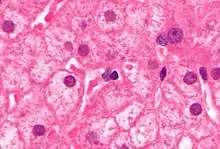

Розроблені ПЛР тести для виявлення і вимірювання кількості ДНК HBV, у клінічних зразках, названі вірусним навантаженням. Ці тести використовуються щоб оцінити стан інфекційності та моніторити лікування.[44] У осіб з високими вірусними навантаженнями, виявляють матово-склоподібні гепатоцити при біопсії.